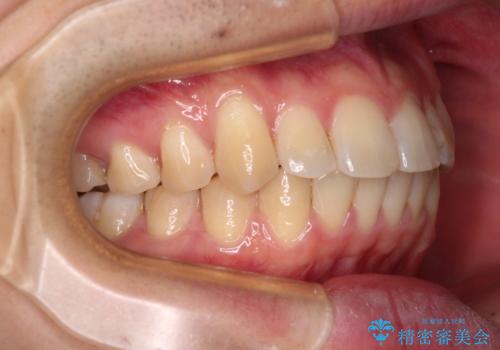

- 上下前歯のデコボコを気にして来院された患者様です。

マウスピース矯正でもワイヤー矯正でも対応可能でしたが、インビザラインによる自己管理が煩わしいとのことで、ワイヤー装置にて矯正治療を行うこととしました。

口元はやや突出感がありましたが抜歯矯正をするほどではないため、舌突出癖を改善するトレーニングをしっかりと行っていただき、現在よりも唇が閉じやすい位置に仕上げていくこととしました。

下顎前歯が思っていた以上に動きが悪く、想定よりも期間がかかってしまいました。

矯正治療後には気になっていた銀歯をセラミックで自然な色に仕上げました。